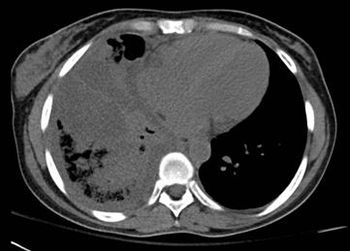

Potential for infection is everywhere for patients with alcoholic cirrhosis.